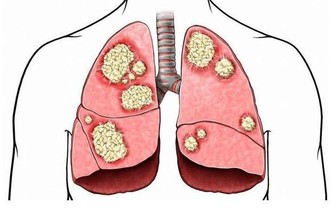

在中醫理論中,“少陽為樞”,足少陽膽經上下貫空身體,就像掌管門戶開合的連接軸一樣,是氣機升降出入的樞紐,對各個臟腑功能都有調節作用。大腿外側正是其循行之處,輕敲此處,可刺激膽經上的穴位,使血氣上升,保證肝、肺等重要臟器得到滋養。此外,肝和膽相表裡,對膽的調理有助清肝火,改善口苦眼乾、胸脅疼痛等肝鬱症狀。